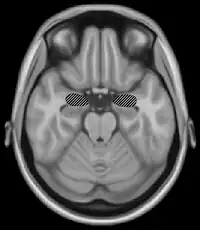

The basal ganglia are a group of nuclei which are located in the medial temporal lobe, above the thalamus and connected to the cerebral cortex. Specifically, the basal ganglia includes the subthalamic nucleus, substantia nigra, the globus pallidus, the ventral striatum and the dorsal striatum, which consists of the putamen and the caudate nucleus.[8] The basic functions of these nuclei deal with cognition, learning, and motor control and activities. The basal ganglia are also associated with learning, memory, and unconscious memory processes, such as motor skills and implicit memory.[4] Particularly, one division within the ventral striatum, the nucleus accumbens core, is involved in the consolidation, retrieval and reconsolidation of drug memory.[9]